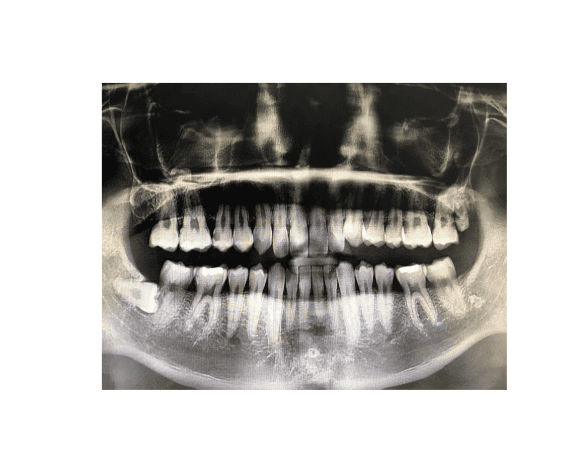

사랑니 발치 여부는 개인의 상태에 따라 신중히 결정해야 합니다. 발치가 필요한 경우는 크게 다음과 같습니다. 첫째, 사랑니가 비스듬히 났거나 매복되어 주변 치아를 압박하는 경우, 둘째, 충치나 잇몸 질환이 반복적으로 발생하는 경우, 셋째, 교정치료를 앞두고 있는 경우입니다. 반면, 사랑니가 정상적으로 나고 주변 치아에 영향을 주지 않는다면 굳이 발치할 필요는 없습니다. 사랑니 발치 여부를 결정할 때는 반드시 전문의와 상담 후 X-ray 촬영을 통해 사랑니의 위치와 상태를 정확히 파악한 후 결정하는 것이 바람직합니다.